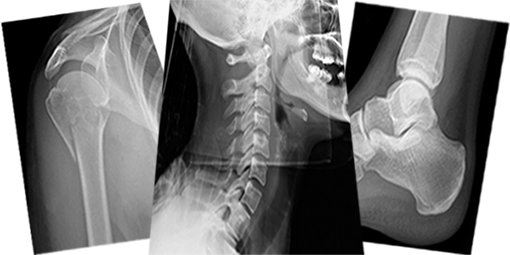

Trauma X-ray Interpretation - Whole Skeleton - Course Completion Assessment

- Trauma X-ray - Upper Limb

- Trauma X-ray - Lower Limb

- Trauma X-ray - Axial Skeleton